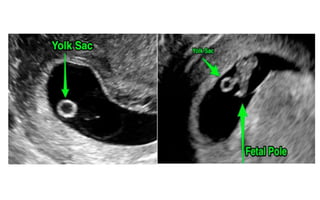

YOLK SAC (YS)

• Before placental circulation is established, yolk sac is the primary source

of exchange between the embryo & mother.

• In a normal early pregnancy, diameter is < 6mm where it’s shape should

be near spherical.

• Natural course: As pregnancy advances, it disappears & sonographically

not detectable after 14 weeks.

• Absence of YS in the presence of an embryo is always abnormal and is

associated with fetal desmise.

• A larger than normal YS is also associated with adverse outcome in the

fetus.

• Visualization of multiple YS is the earliest sign of a poly-amniotic

pregnancy (e.g. twins)

YOLK SAC (YS) •Before placental circulation is established, yolk sac is the primary source of exchange between the embryo & mother. • In a normal early pregnancy, diameter is < 6mm where it’s shape should be near spherical. • Natural course: As pregnancy advances, it disappears & sonographically not detectable after 14 weeks.

• 15.

• Absence ofYS in the presence of an embryo is always abnormal and is associated with fetal desmise. • A larger than normal YS is also associated with adverse outcome in the fetus. • Visualization of multiple YS is the earliest sign of a poly-amniotic pregnancy (e.g. twins)